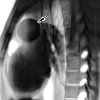

Трансторакальная пункция кисты средостения с дренированием и склерозированием

Трансторакальная пункция кист средостения с дренированием и отвердением. Малоинвазивное вмешательство, включая чрескожную аспирацию содержимого кистозных образований тонкой иглой, дренирование и облитерацию остаточной полости склерозирующими препаратами. Вмешательство проводится с соматически отягощенным диагнозом, наличием противопоказаний для обширной операции, с бессимптомными кистами средостения небольшого размера. Трансторакальная пункция и дренирование кист средостения выполняются под ультразвуковым контролем. Остаточная полость кисты элюируется путем введения 96% раствора этилового спирта.